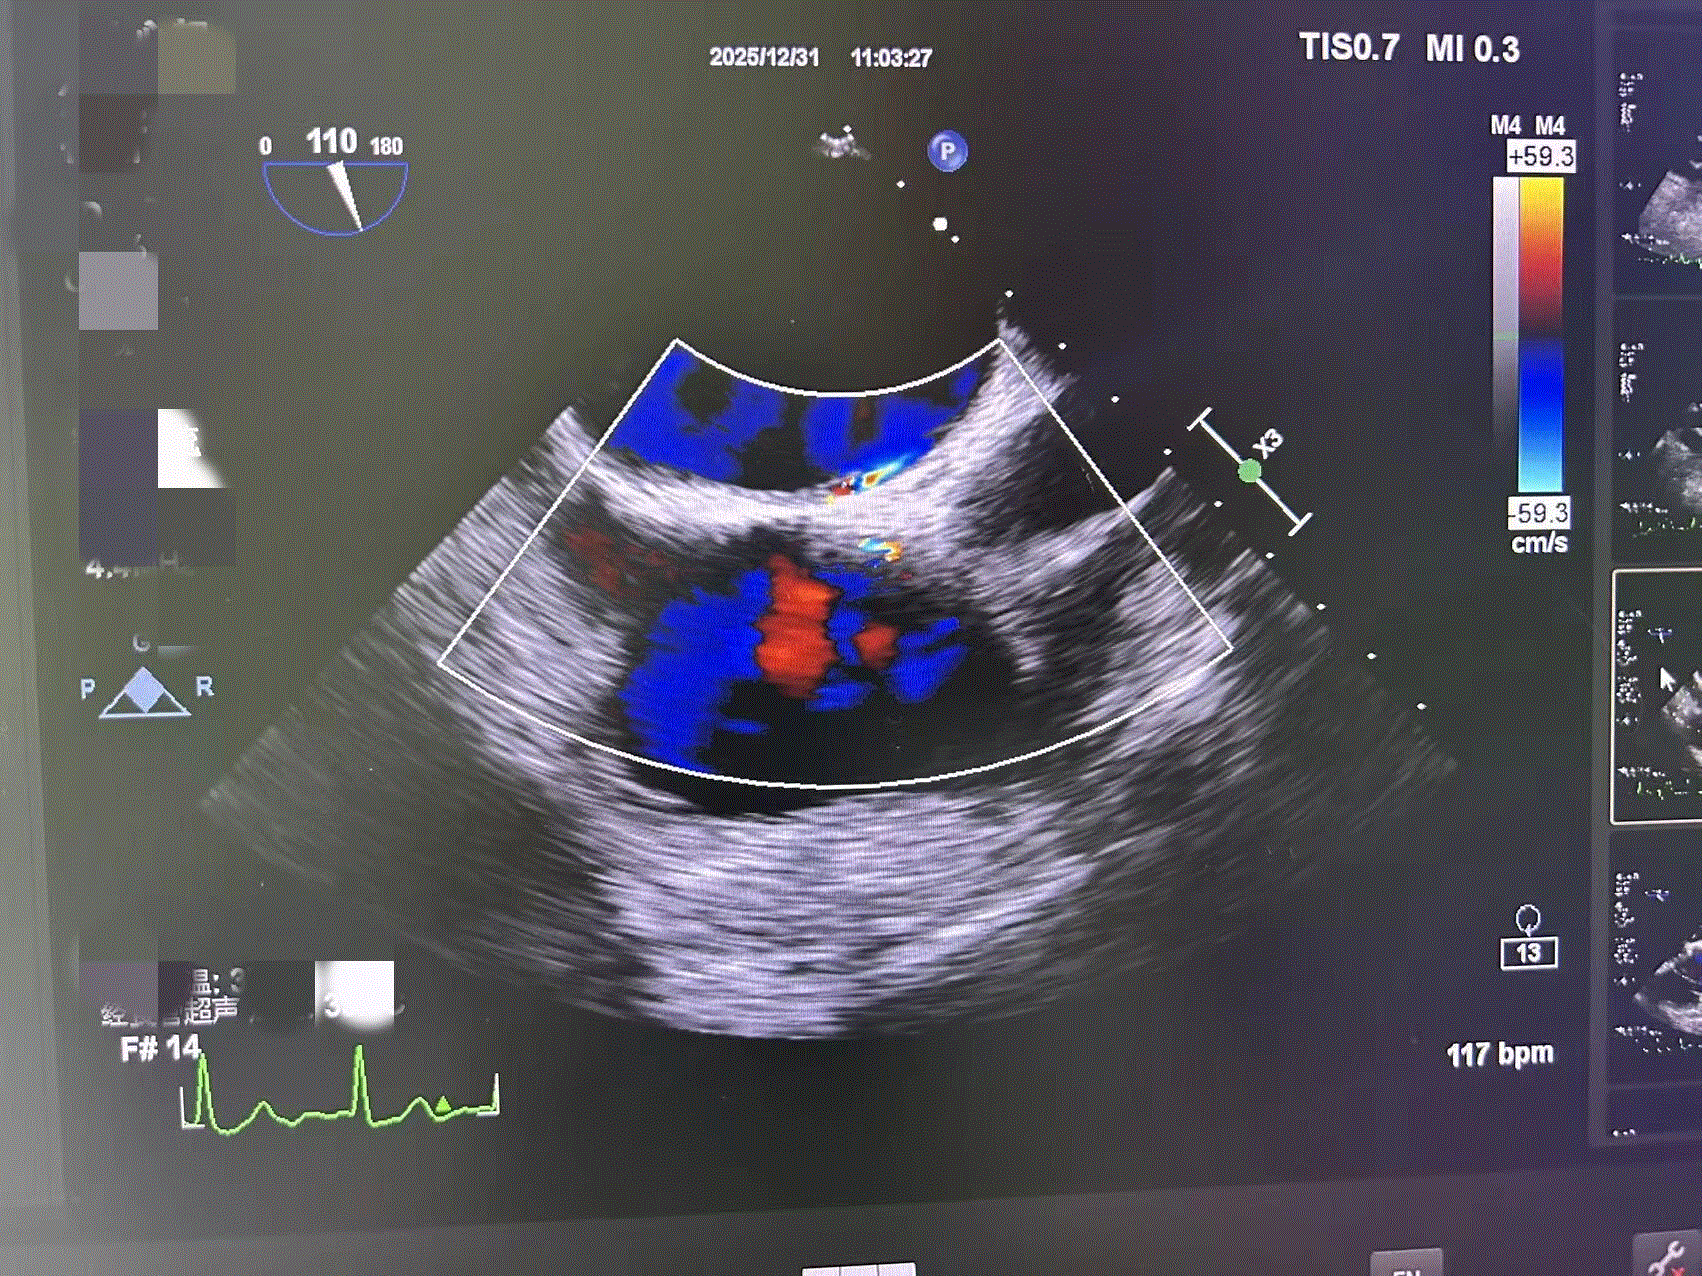

清晰显示二尖瓣、主动脉瓣等瓣膜的形态、厚度、启闭情况,准确判断瓣膜狭窄或关闭不全的程度,为手术方案的制定提供关键依据。

是诊断左心房、左心耳血栓的“金标准”,尤其对于房颤患者术前血栓筛查至关重要;同时能清晰识别心内膜炎患者心脏瓣膜上的赘生物,指导抗感染治疗。